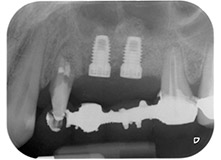

Fig. 1: 58-year-old patient. Preoperative radiograph showing an apical periodontal lesion at tooth 24 and horizontal loss of alveolar bone in the second quadrant.

A 58-year-old female patient complained of pain and increased mobility of her bridge abutment tooth 24. Periodontal inflammation was present with pocket depths of 7 mm mesiobuccally and more than 12 mm distally, as well as third-degree furcation involvement. Moreover, the radiograph revealed an extensive periodontal lesion around the apical region of the (alio loco) endodontically pretreated tooth 24 (Fig. 1).

One year earlier, teeth 25 and 26 had been extracted due to trauma and for endo-perio reasons, prior to the placement of the bridge. A combined endo-perio lesion was diagnosed for tooth 24, of unclear aetiology. The patient wanted to keep her bridge abutment teeth 24 and 27 and would not accept a final, or even temporary, removable prosthesis. Therefore, it was agreed to make all efforts to retain both teeth, in spite of their poor prognosis as based on radiological and clinical findings.

Placement of two submerged implants was planned at sites 25 and 26, in a surgical session with open periodontal debridement and apicoectomy of tooth 24. Due to the vertical bone deficiency at the future implant site, an internal sinus augmentation was also planned.